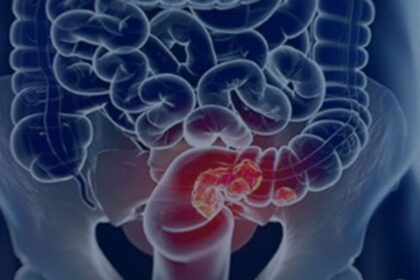

Pacientes com câncer colorretal são diagnosticados em estágio avançado

Lançado nesta quinta-feira (27), quando se comemora o Dia Nacional de Combate…